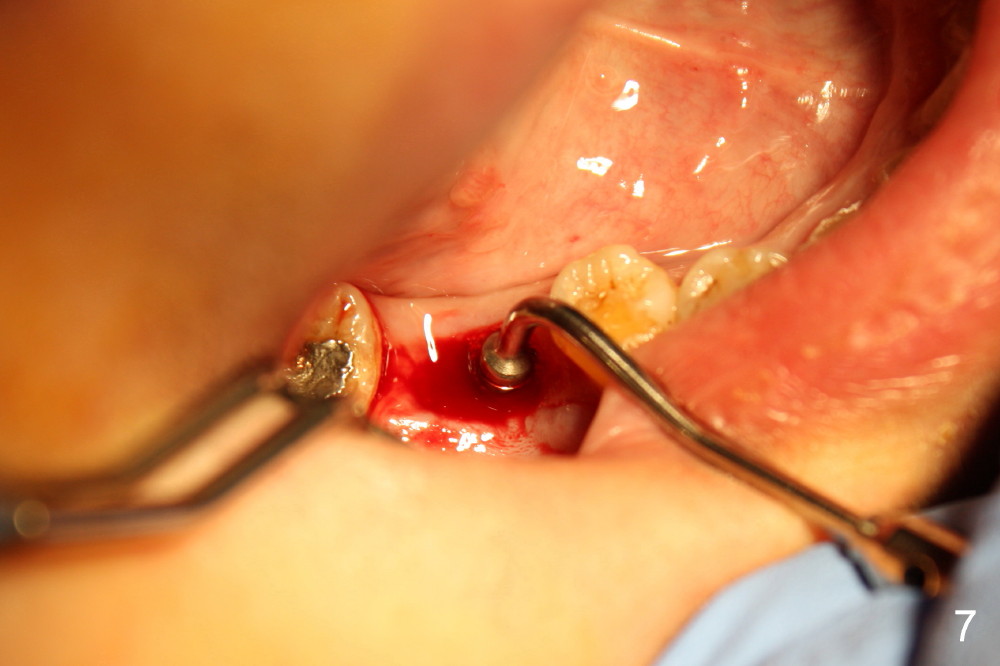

The socket of #30 heals one month after extraction (Fig.1 *). What is unexpected is that the alveolus has started to shrink (follows arrowheads). It is also unexpectedly easy to tap in RT2 (flapless). With insertion of a 2.0 mm pilot drill, PA reveals that osteotomy is not inside the septum (Fig.2 S). Redirecting osteotomy with the same pilot drill leads to insertion into the septum, but the upper end of the pilot drill should be moved mesially in next steps (arrow). With that and treatment plan in mind, combination of osteotomes, Bicon reamers and taps results in right trajectory (Fig.4 * (5x20 tapered tap), Fig.5 (6x17 tapered tap)). Harvested bone (Fig.6) is transferred to the mesial socket and condensed (Fig.7). Insertion torque of 6x17 mm implant is more than 60 Ncm. The lower end of the implant remains in the center of the septum (Fig.8 <). The gingiva contacts the implant tightly (Fig.9, 10) except mesiobucally (Fig.9 <). Periodontal dressing is used to protect the wound (Fig.11,12).